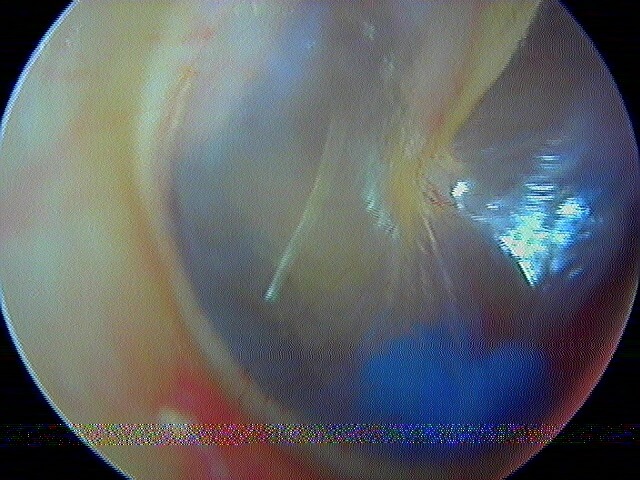

3/2 barotraumatique

– stade I : hyperhémie du manche du marteau et de la pars flaccida ;

– stade II : tympan rétracté, congestif, immobile

– stade III : aspect d'otite séromuqueuse

– stade IV : aspect otite séro-hémorragique, otohématome

– stade V : perforation

Ici des stades V perforés